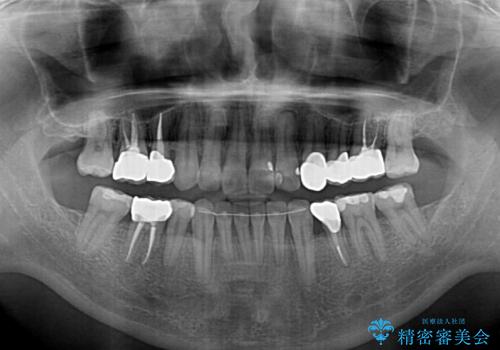

その後、以前行った抜歯矯正の後戻りをインビザライン・ライトにより改善し、むし歯や銀歯はオールセラミッククラウンにて補綴治療することとしました。

痛みは速やかに引き、銀歯や黒く変色したむし歯がセラミッククラウンで自然な色合いに仕上がり、患者様には大変満足していただきました。